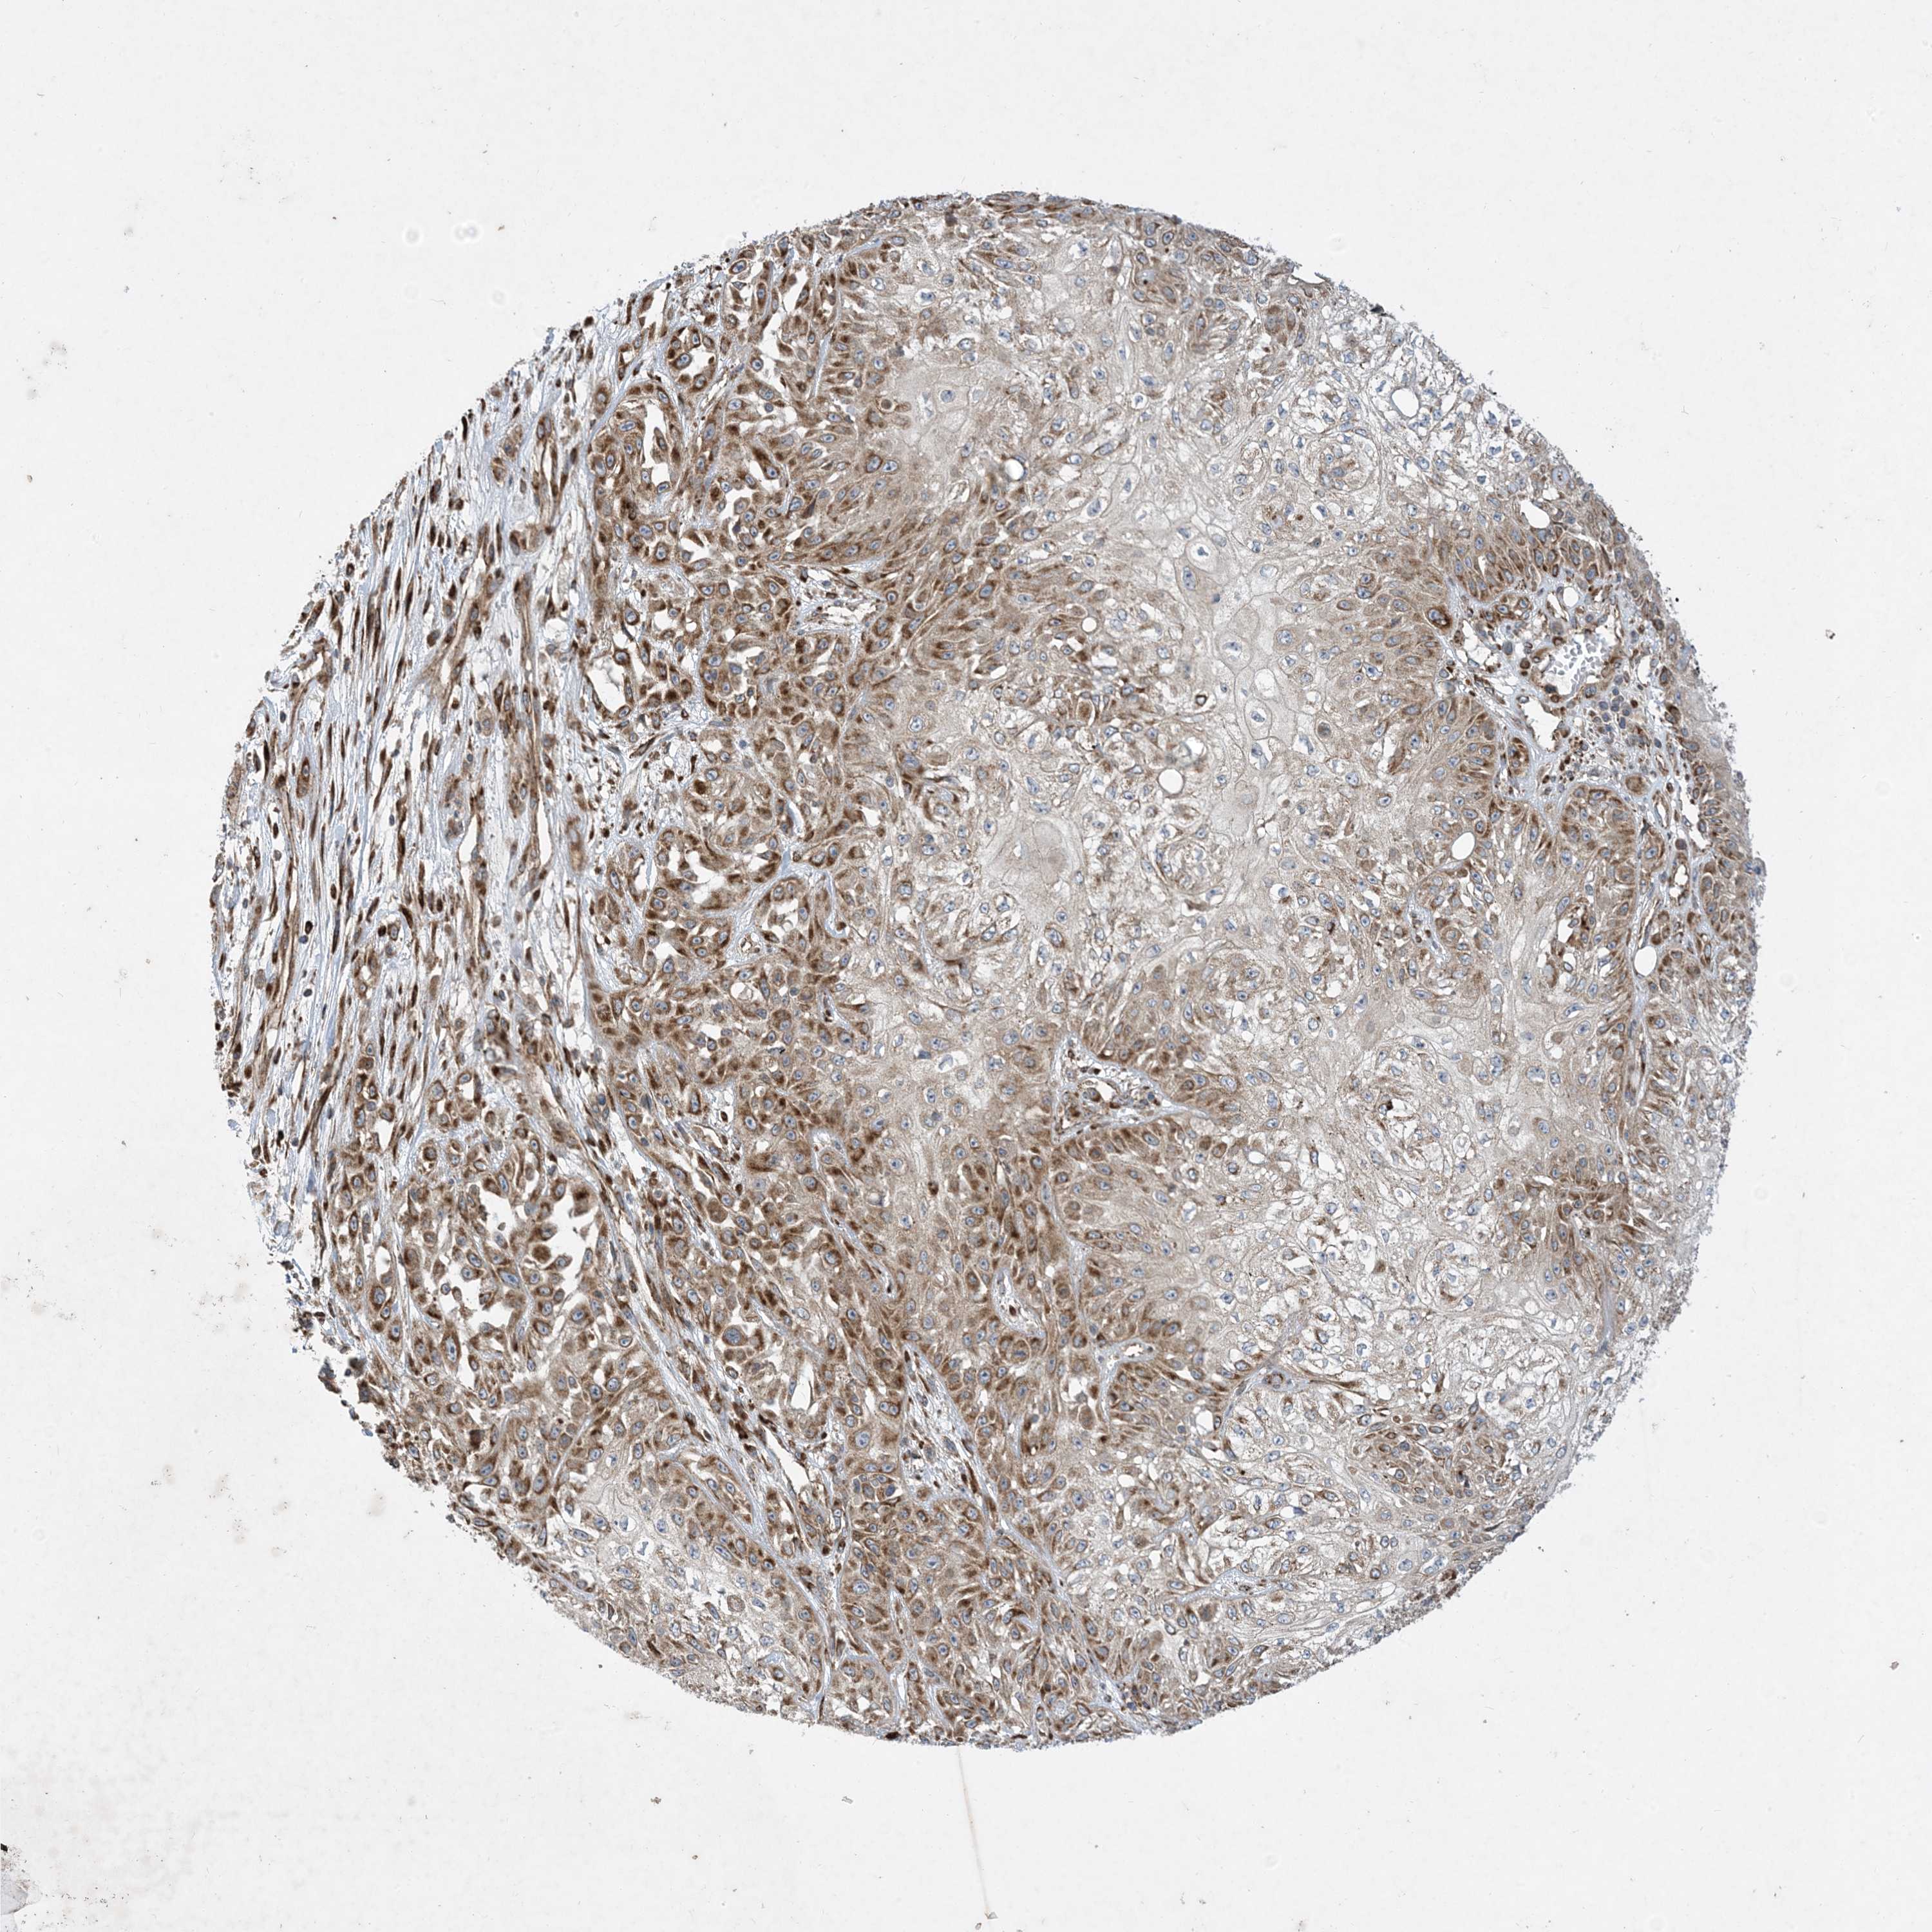

SKIN CANCER - Protein expressioni

A mouse-over function shows sample information and annotation data. Click on an image to view it in a full screen mode. Samples can be filtered based on level of antibody staining by selecting one or several of the following categories: high, medium, low and not detected. The assay and annotation is described here.

Antibody stainingi

Antibody staining in the annotated cell types in the current human tissue is reported as not detected, low, medium, or high, based on conventional immunohistochemistry profiling in selected tissues. This score is based on the combination of the staining intensity and fraction of stained cells.

Each image is clickable and will lead to virtual microscopy that enables deeper exploration of all samples and also displays staining intensity scores, fraction scores and subcellular localization as well as patient and tissue information for each sample.

Antibody HPA035599

Staining

High

Intensity

Strong

Quantity

>75%

Location

Nuclear

Basal cell carcinoma

Squamous cell carcinoma, NOS

Squamous cell carcinoma, metastatic, NOS